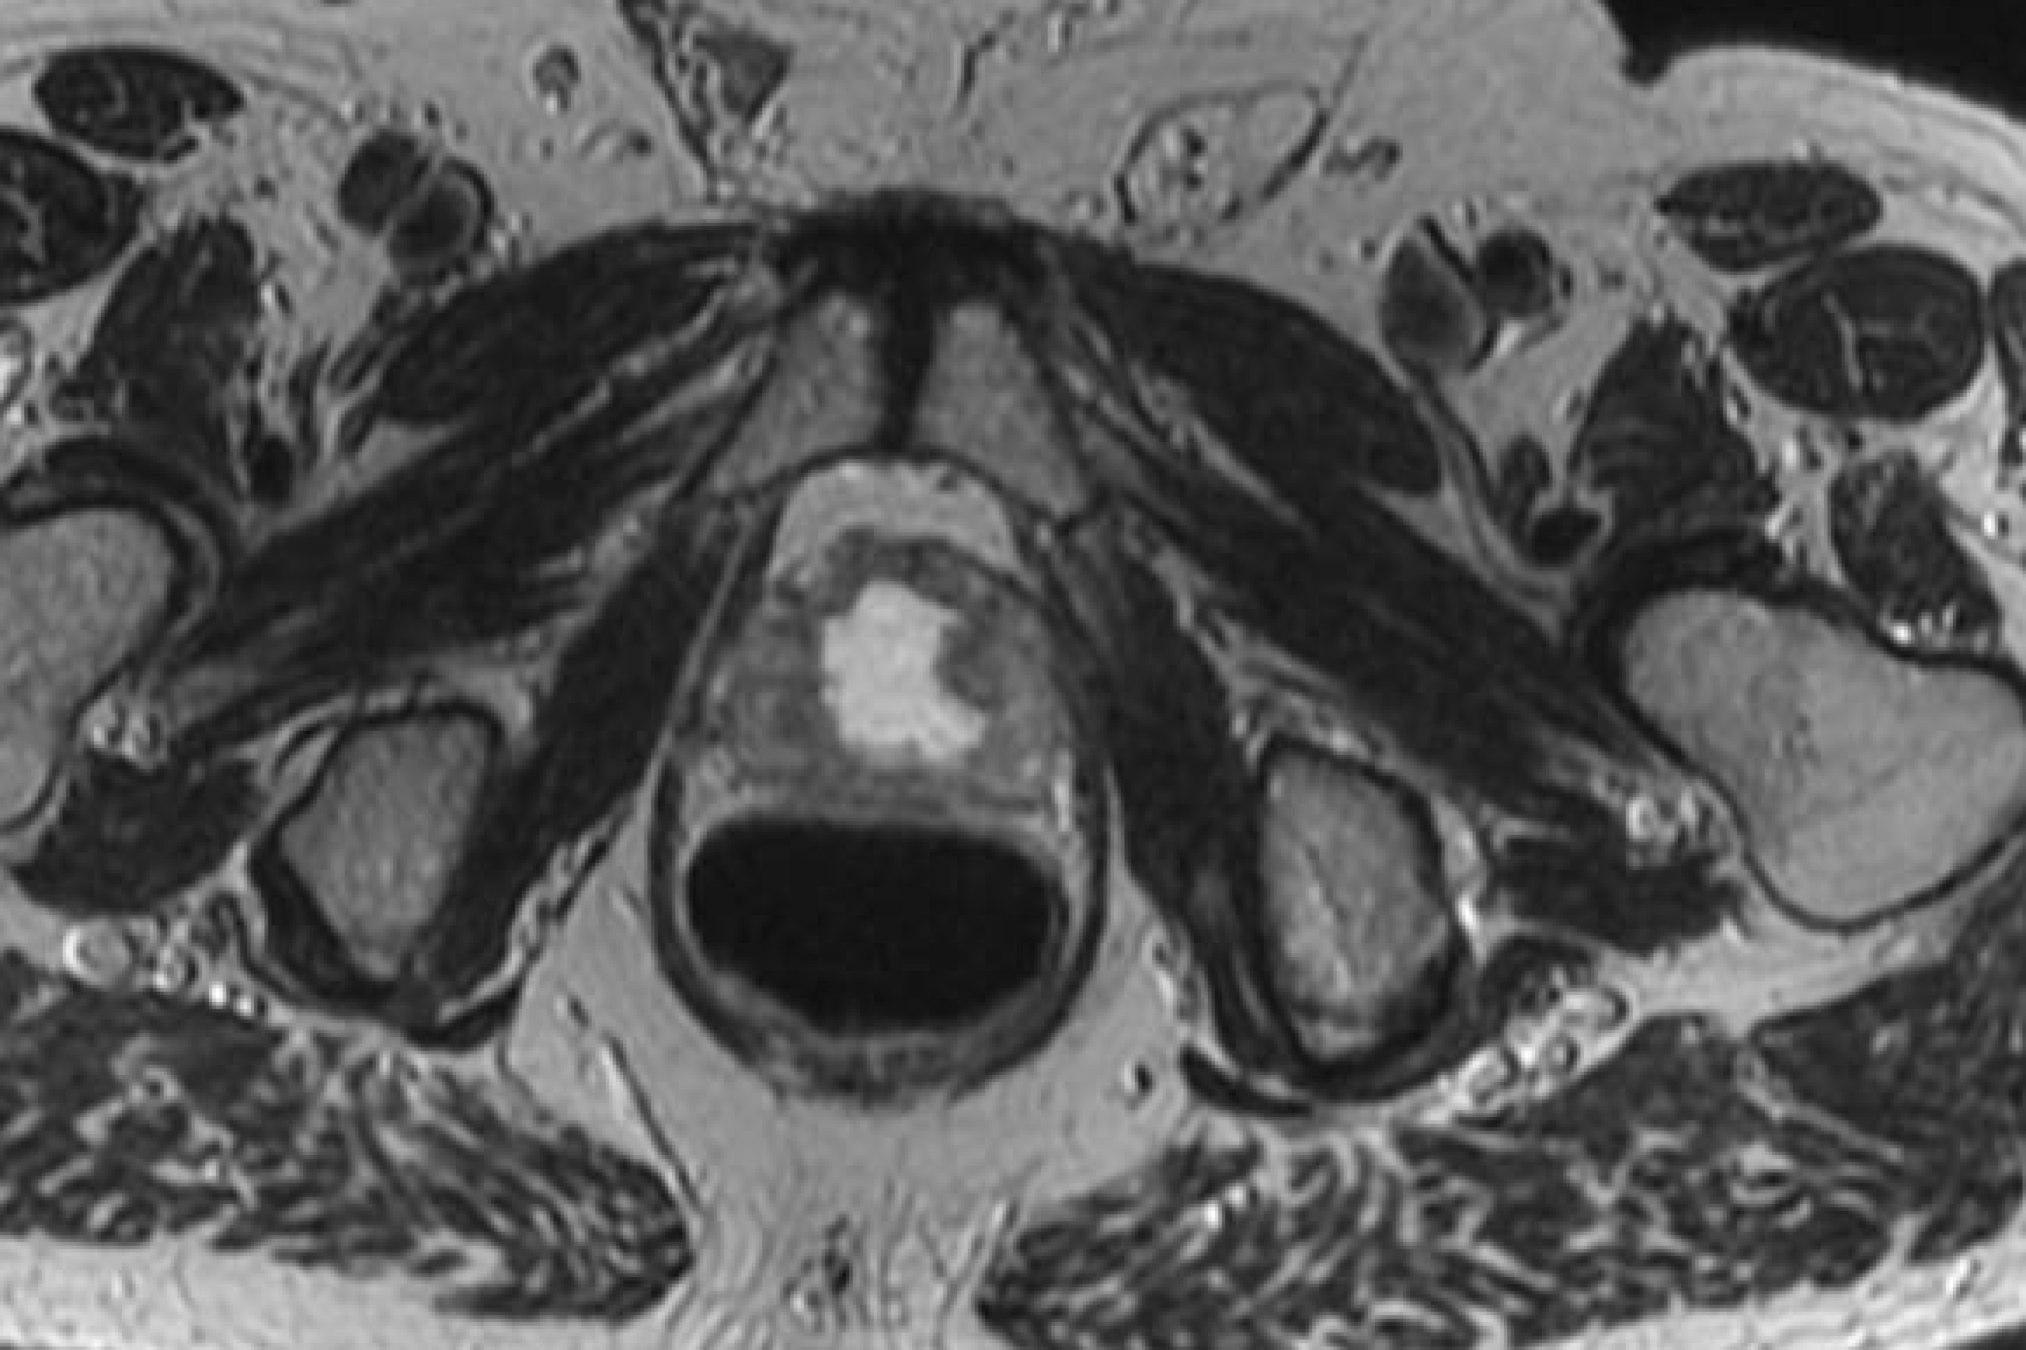

Prior TURP may also be a contraindication as this may allow seeds to overdose the urethra, which could lead to stricture or post-implant incontinence. With modern peripheral loading techniques, this may be less a contraindication than previously thought as complications have decreased. Linked seeds may be advantageous in this setting. Before any brachytherapy in a patient with a history of TURP can be considered, detailed imaging of the extent of TURP should be obtained and considered mandatory. T2 MRI and T1 post gadolinium will be helpful.

This is probably not the ideal prostate candidate for implant.